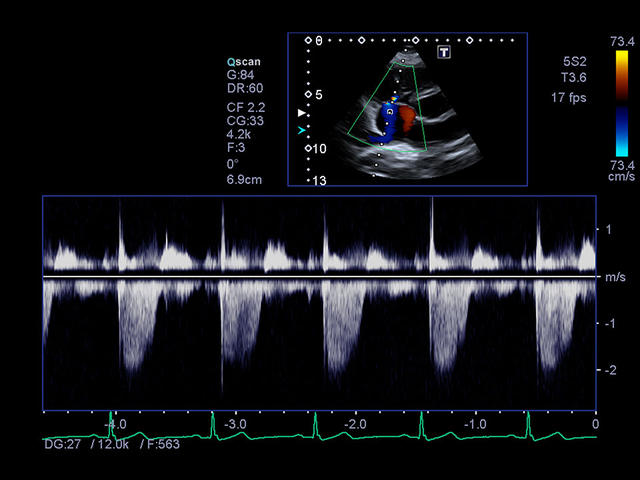

- Кардиология

- Импульсно-волновой допплер - Pulsed Wave Doppler (PWD).

- Цветной, энергетический допплер - Colour Doppler Imaging/ Color Angio (CDI/CA).

- Тканевой допплер - Tissue Doppler Imaging (TDI).

- Модуль высокой частоты повторения импульсов - High pulse rate frequency (HPRF).

- Оценка глобальной и локальной сократимости ЛЖ сердца в 2D: 2D Wall Motion Tracking

- Стресс эхокардиография: Stress Echo